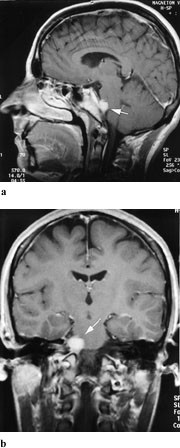

Cisternale lesjoner av abducensnerven gir isolert abduksjonsparese og forekommer ved økt intrakranialt trykk eller ved svulster i clivusområdet, som meningeom, kordom eller metastaser (fig 4). Abducensparese med hodepine er karakteristisk ved clivuskordomer. Svulsten vokser langsomt, og kan gi symptomer i form av intermitterende dobbeltsyn flere år før det er andre nevrologiske funn (11). Inflammatoriske tilstander i forbindelse med mellomørebetennelse kan bre seg til os petrosus og gi det klassiske bildet av Gradenigos syndrom, som ved siden av abducensparese består av ipsilateral facialisparese, ipsilaterale ansiktssmerter og nedsatt hørsel.